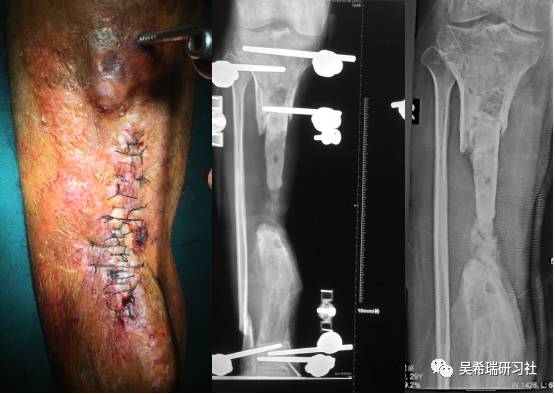

病例7

小腿骨折继发感染骨髓炎反复皮瓣9个月未下地骨质疏松继发肥胖

TIPS:9个月反复皮瓣未下地骨质严重疏松病灶清除后应用表面羟基磷灰石涂层骨圆钉半开放植骨 + 骨搬移骨水泥设计为自行吐出伤口开放换药走路骨质改善、骨愈合治疗足下垂